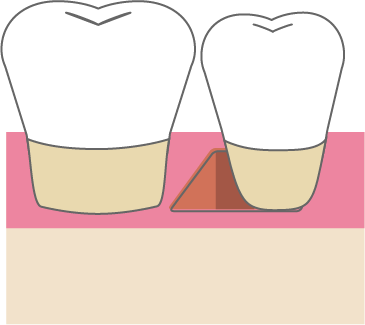

歯周組織再生療法は施術の難易度が高く、ほとんどの歯科では扱っていない内容です。